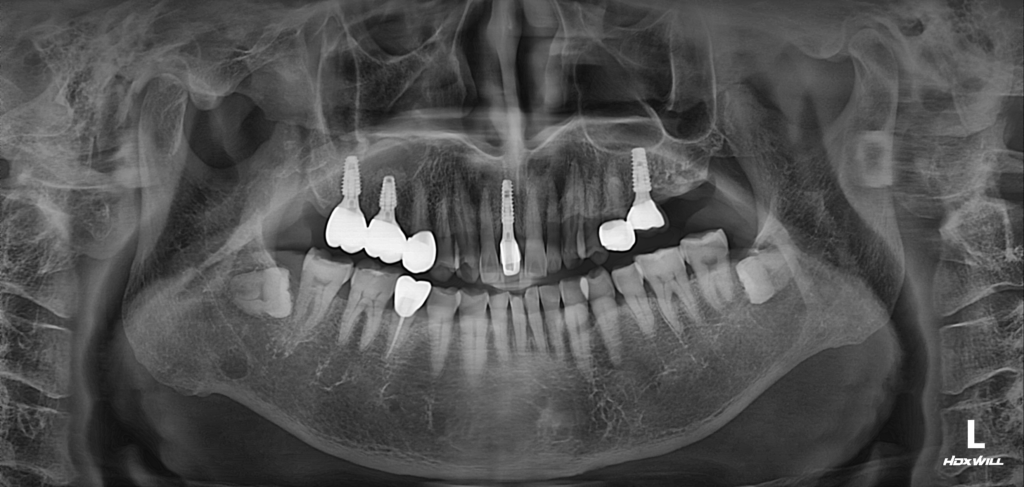

술후 사진

두 번째 작은 어금니인 #15 치아는 상태가 양호해, 굳이 제거할 필요가 없다고 판단하여 보존하기로 했습니다. 이후 계획한 대로 #16, #17 부위에 충분한 골높이를 확보했고, 그 결과 임플란트가 안정적으로 식립된 모습을 확인할 수 있었습니다.

불필요하게 측방접근(Lateral) 골이식까지 진행하지 않아 환자분의 부담을 최소화할 수 있었고,

전체 치료 과정 역시 비교적 수월하게 마무리되었습니다. 시술 후에도 만족도가 높아 현재는 임플란트에 잘 적응하시며 정기 검진을 통해 영도치과에서 꾸준히 관리받고 계십니다.